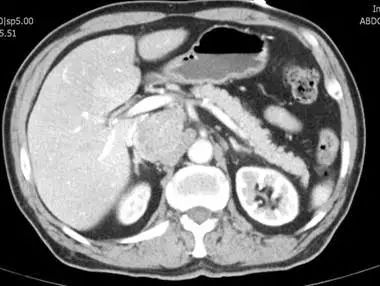

入住我院后查上腹部增强CT提示:腔静脉与腹主动脉间隙肿块,最大径约59mm(比三年前明显增大),考虑异位嗜铬细胞瘤,查血儿茶酚胺是正常值的20倍以上。上海市中西医结合医院普外科主任杨孙虎医师和泌尿外科专家刘剑新副院长反复研究病情,并由医务处组织泌尿外科、影像科、心病科、内分泌科、麻醉科、ICU、肿瘤科、输血科等学科的专家进行了MDT讨论,决定为患者实施腹膜后肿瘤切除术,并制定了周密的围手术期准备方案,包括术前控制血压、心率、扩容,术中因为挤压肿瘤导致的高血压危象和肿瘤切除后低血压的纠正等等。